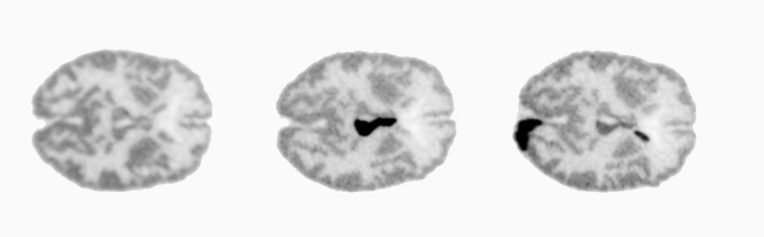

A preclinical prototype to examine the head of mice has also been built with the same technology. The brain of a mouse has a size of only few millimetres and therefore to be able to visualize the detailed structure of its head and quantify, for instance, the amyloid deposit content, is very challenging.

The spatial and temporal resolution of the preclinical PET scanner for examining the head of a mouse are 0.8mm and 200picoseconds (ps), respectively. Furthermore, an inner gamma-ray detector layer closer to the brain has been built with a timing resolution of 130ps.